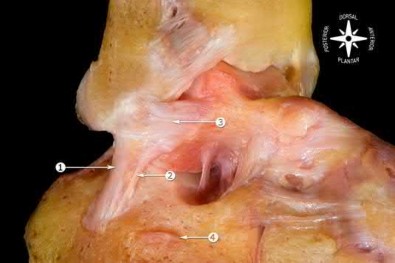

The anteromedial facet is highlighted in yellow as displayed in Illustration A. Illustration B depicts the lateral collateral ligament injury also evident during

varus stress fluroscopic examination, due to tension failure of the LCL off its humeral origin during the various mechanism.

Anteromedial coronoid facet fracture and LCL injury following an elbow dislocation is commonly associated with varus posteromedial rotatory instability. Varus and posteromedial rotation force on the forearm results in rupture of the LCL from its humeral origin. As the LCL ruptures, the medial coronoid process is fractured as it impacts against and under the medial trochlea. Fracture involvement of the sublime tubercle, where the MCL attaches, can lead to more instability. Ulnar neuropathy can be seen following this injury pattern but AIN and PIN nerve palsy do not commonly characterize this injury pattern.